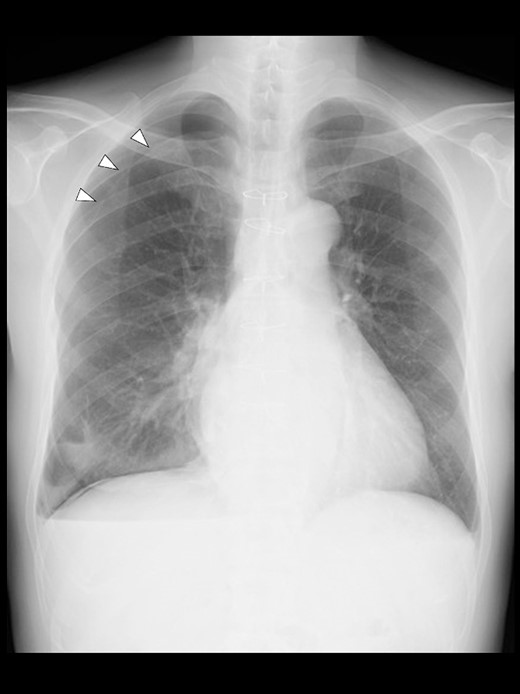

A 57-year-old male, 178 cm and 69 kg, was scheduled for a laparoscopic appendectomy for chronic appendicitis. The patient had undergone mitral valve repair for infective endocarditis via a median sternotomy 16 years before and minimally invasive esophagectomy (MIE) with intrathoracic anastomosis using a gastric tube for esophageal cancer 5 years before. Preoperative tests, including a chest radiograph (Fig. 1), were unremarkable. The computed tomography (CT) revealed no emphysematous lung cyst. Anesthesia was induced with intravenous remifentanil (0.3 μg/kg/min) and propofol (100 mg). Intravenous rocuronium (50 mg) was administered to facilitate tracheal intubation. Anesthesia was maintained with inhaled sevoflurane (1.5%) and intravenous remifentanil (0.1–0.3 μg/kg/min). The lungs were ventilated with a volume-guarantee pressure-controlled mode employing an inspired oxygen concentration of 35%. Percutaneous arterial oxygen saturation (SpO2) was maintained at 96%–100%. In addition to local anesthetic wound infiltration, intravenous fentanyl (300 μg) and acetaminophen (1000 mg) were administered for immediate postoperative analgesia. Operation and anesthesia times were 121 and 156 min, respectively. The infusion volume was 1350 ml. Emergences from anesthesia and extubation were uneventful. SpO2 in the postanesthesia care unit was maintained above 95% without supplemental oxygen. The patient did not complain of chest pain or dyspnea.